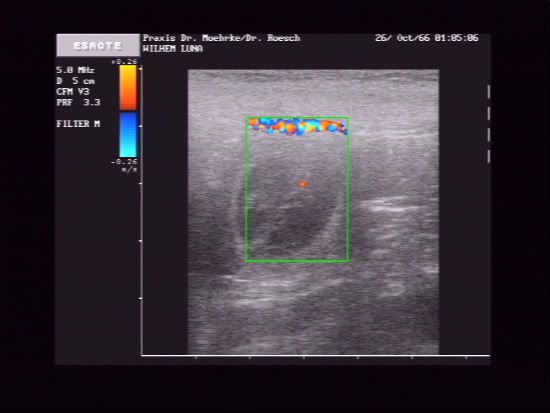

Het duurt nog wel even voordat ze daadwerkelijk geboren worden, maar de echo was afgelopen week in ieder geval positief.

Hutch heeft een teefje uit Duitsland mogen dekken in april. Als alles verder goed gaat worden de pups geboren rond 23 mei.

Vandaag kreeg ik een aantal foto's van de echo van afgelopen donderdag

En hier is een hartje te zien